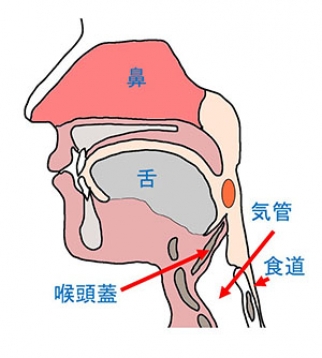

口から喉にかけての部位の名称(鼻腔・口腔・上咽頭・中咽頭・下咽頭・声帯)